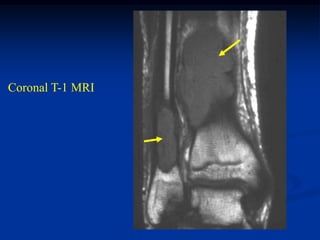

Case #432

4 year male

EG mid fibula